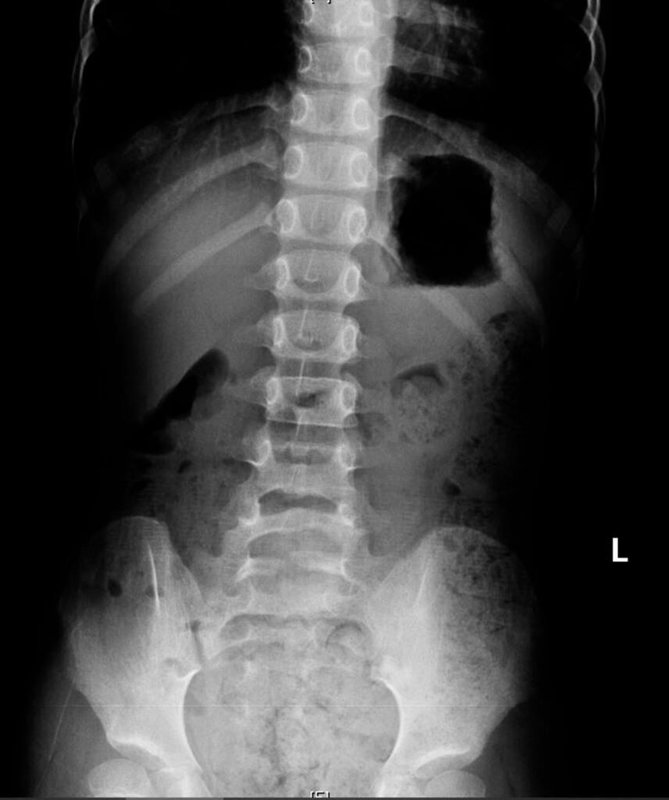

(中央社記者林巧璉高雄28日電)高雄一名11歲男童近日因腹痛、冒冷汗、嘴唇發紫、手腳冰冷被送到阮綜合醫院急診,X光檢查發現滿肚子都是大便;醫師提醒,家長要建立孩子規律排便習慣,可在飯後便意強時提醒上大號。

11歲男童近日因腹痛、嘴唇發紫送急診,經X光檢查診斷為便秘。灌腸後排出大量糞便,症狀立刻緩解。男童母親表示,孩子習慣邊上廁所邊玩手機,常被催促太久才匆忙結束,也不清楚是否排便乾淨。